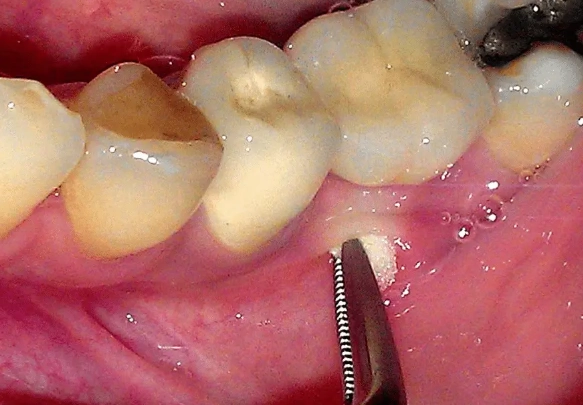

| Incision & Drainage (I&D) | Making a small cut in the gum to drain pus, relieving pressure. | Emergency measure for severe swelling, done alongside RCT or antibiotics. | Not a standalone cure. Must be followed by definitive treatment. |